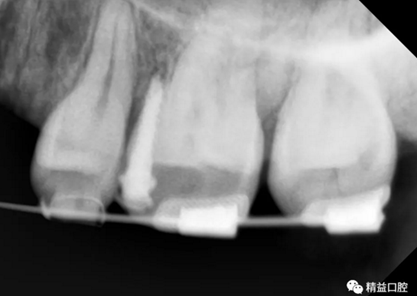

初次看到俊的牙片,我也驚訝到了,畢竟才27歲,上下門牙牙根吸收得非常嚴(yán)重,如果矯正,其中的風(fēng)險還是非常大的。

從片子上可以清除看到,上牙門牙牙根吸收非常厲害。

李醫(yī)生考慮到俊上下門牙吸收嚴(yán)重,前牙突度大,建議先拔除上頜兩顆四,對上牙進行內(nèi)收,后期看矯正效果再對下牙進行處理。

為了保證矯正效果和整體牙齒健康,李醫(yī)生在矯正過程中不斷根據(jù)每次牙齒移動的情況,對所施加的矯正力以及每次復(fù)診的時間進行精細(xì)的調(diào)整,在放慢矯正速度的同時,以更加輕柔的力量來拉動牙齒移動。事實證明一切OK,上牙的內(nèi)收效果非常的好。